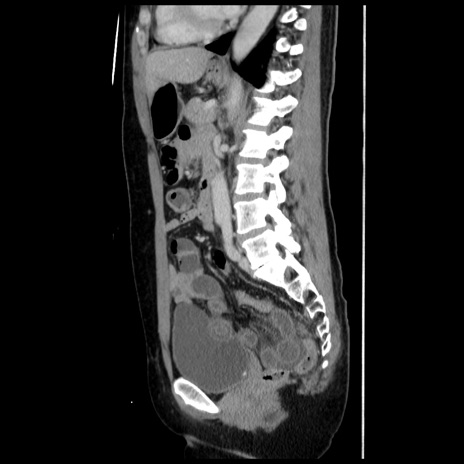

症例10(矢状断像)

【症例】 50歳代女性

【主訴】 腹痛

【現病歴】前日生レバーを食べた。今朝に排便あり。 昼前に突然発症の腹痛を生じ、当院救急外来を受診した。

【既往歴】 子宮筋腫にてで子宮全摘後

【身体所見】 意識清明、腹部:平坦、軟、下腹部やや左を中心に圧痛・反跳痛あり、筋性防御あり

【データ】WBC 7800、CRP 0.07